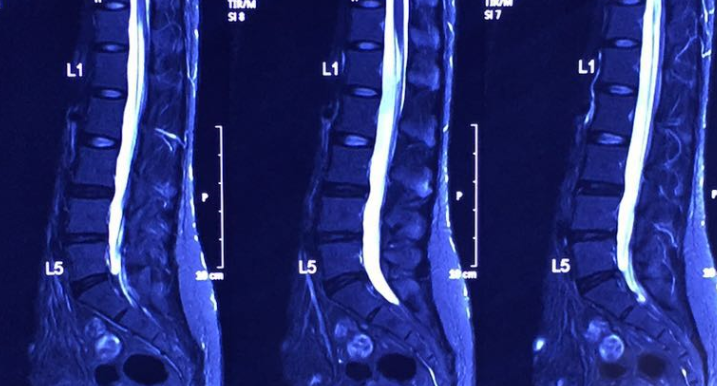

Illustrated MR 3, MR 4

In January 2016, the degree of herniated disc has been greatly improved, and the previously compressed part of the nerve root has also disappeared.